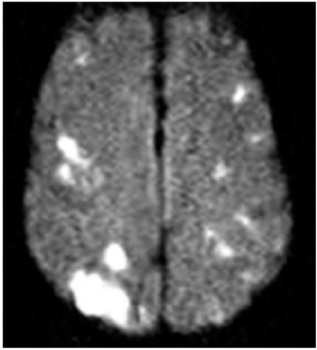

A 45 y/o woman with hypertension is resuscitated after a cardiac arrest. On day three she is able to move her face, hands, and feet, but is unable to move her limbs. A T2W1 MRI is taken at this time and is attached.

What is the general pathogenesis behind her symptoms and the MRI findings?

Hypotension secondary to cardiac arrest caused ischemia within the cerebrum, which has damaged her primary motor cortex bilaterally.

What cellular change is causing the bright vertical bands in each hemisphere?

Cytotoxic edema secondary to ischemia. The ischemia disrupts metabolism, which shuts down the Na+/K+/ATPase and causes cellular retention of Na+ and water.

Recall that on a T2W1 MRI, fluid (including water and CSF) is bright (as well as fat).

Why is the cellular change visaulized by the MRI localized to vertical bands?

This injury is a watershed infarction between the areas perfused by the ACA and MCA. The MCA area of the brain is especially susceptible to ischemia, and so its watershed area with the ACA will be the first to suffer. The bright vertical bands show cellular injury in the watershed zones across the entire cerebrum.

Why is the woman able to move her face, hands, and feet, but not her limbs?

Watershed injury across the the primary motor cortex tends to affect the proximal limbs and trunk much more severely than the hands, feet, and face.

• This is partially due to the watershed area’s location being centered over the motor homonculus’ area for the limbs and trunk,

• And partially due to the trunk and limbs being relatively small areas of the homonculus while the hands, feet, and face take up a large area of it (more sensitive/precise moving structures)

• Thus, even a small ischemic area can cause relatively severe truncal or limb weakness, whereas the majority of the larger face, hand, and foot regions tend to be spared.